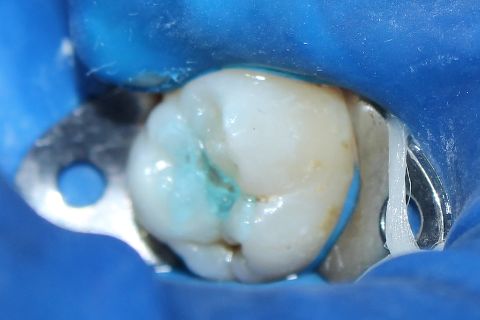

isolamento absoluto

profilaxia da cavidade com clorexidina a 0,2%

condicionamento ácido - ácido fosfórico a 37%

Preenchimento da cavidade pulpar com resina flow

Incrementos de Resina Composta Esmalte cor A2 Z350